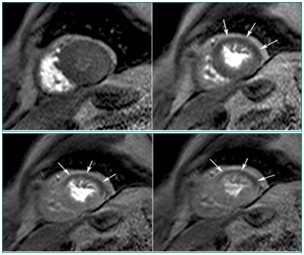

正常心肌

心肌灌注(病例-心肌梗死)